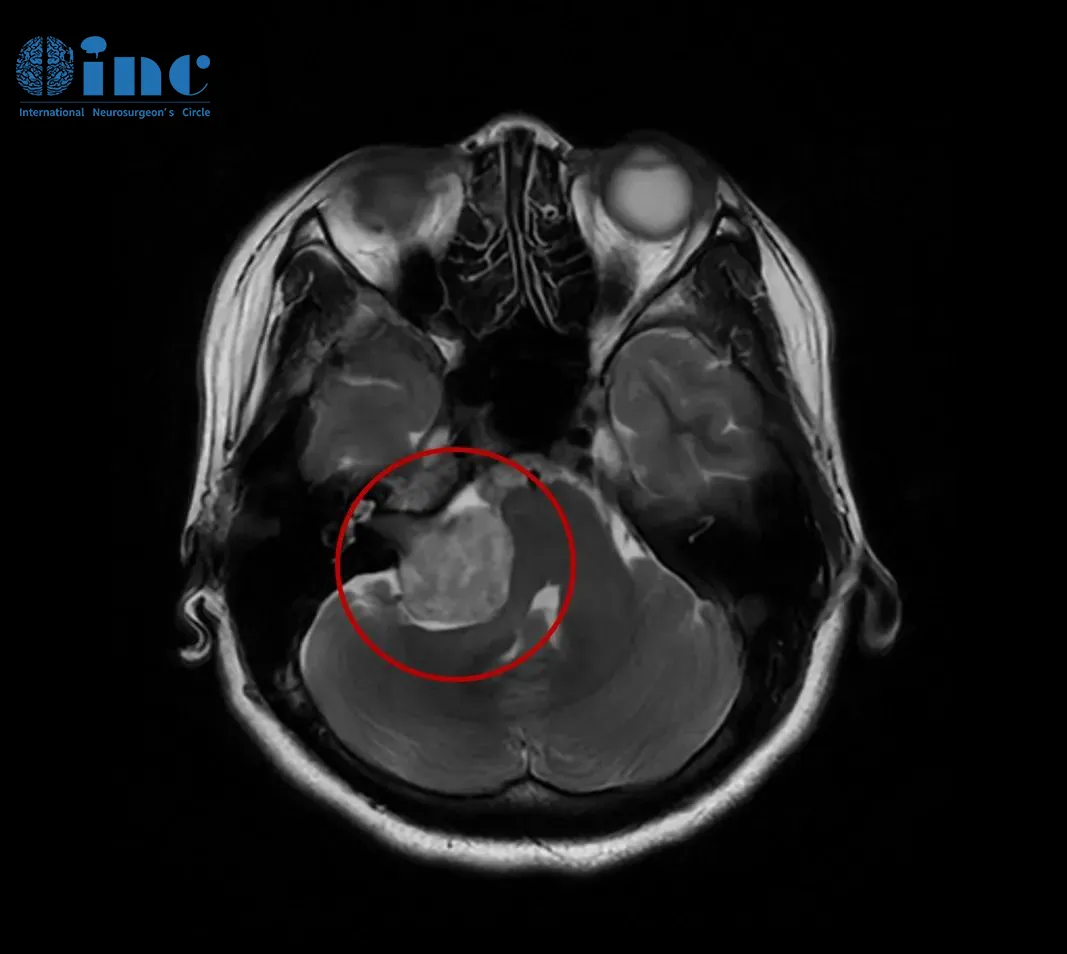

30余岁女性患者2019年始发耳部闷胀感,多次检查未见异常。2021年症状加剧,出现站立不稳、视力下降等表现,MRI确诊为3.5厘米听神经瘤压迫脑干。经过个体化手术入路结合神经电生理监测,实现肿瘤全切并保留面部功能。术后两年随访无复发迹象。